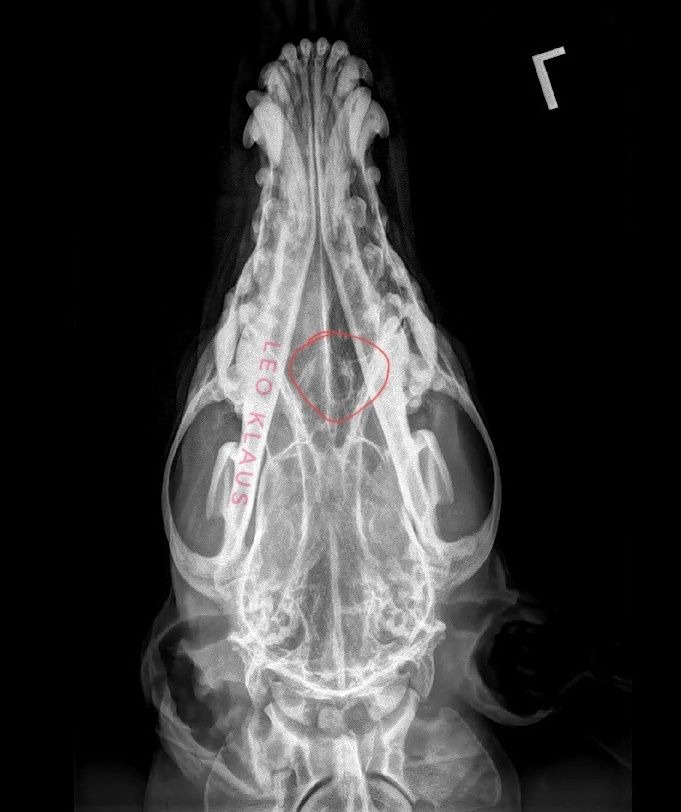

He went in on December 4th, was sedated, and got an X-ray done on his head and chest. This told us nothing aside from yes - there is a hole in his bone. There's no mass or tumor, there's no fuzziness on the edges of the hole, and his lungs look good. My vet, who has been seeing Sage since I got him, doesn't believe it to be cancer, though he also said unilateral nosebleeds are rarely not cancer. But, X-rays can only pick up so much in terms of other possibilities - Could it be a foreign body like a foxtail? A fungal infection like Aspergillosis? Neither of those show up on X-ray.